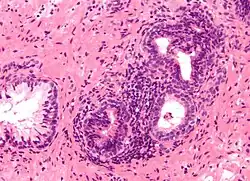

The prostate consists of glandular and connective tissue.[2] Tall column-shaped cells form the lining (the epithelium) of the glands.[2] These form one layer or may be pseudostratified.[4] The epithelium is highly variable and areas of low cuboidal or flat cells can also be present, with transitional epithelium in the outer regions of the longer ducts.[10] Basal cells surround the luminal epithelial cells in benign glands. The glands are formed as many follicles, which drain into canals and subsequently 12–20 main ducts, These in turn drain into the urethra as it passes through the prostate.[4] There are also a small amount of flat cells, which sit next to the basement membranes of glands, and act as stem cells.[2]

The connective tissue of the prostate is made up of fibrous tissue and smooth muscle.[2] The fibrous tissue separates the gland into lobules.[2] It also sits between the glands and is composed of randomly orientated smooth-muscle bundles that are continuous with the bladder.[11]

Over time, thickened secretions called corpora amylacea accumulate in the gland.[2]

Microscopic glands of the prostate -

Microanatomy of a prostatic gland, showing both luminal cells and surrounding basal cells. H&E stain. -